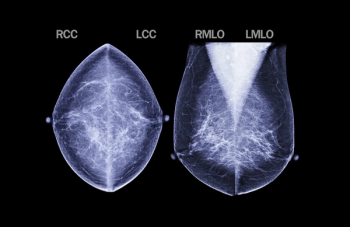

In multiple mammography datasets with the original radiologist-detected abnormality removed, deep learning detection of breast cancer had an average area under the curve (AUC) of 87 percent and an accuracy rate of 83 percent, according to research presented at the recent Society for Imaging Informatics in Medicine (SIIM) conference.